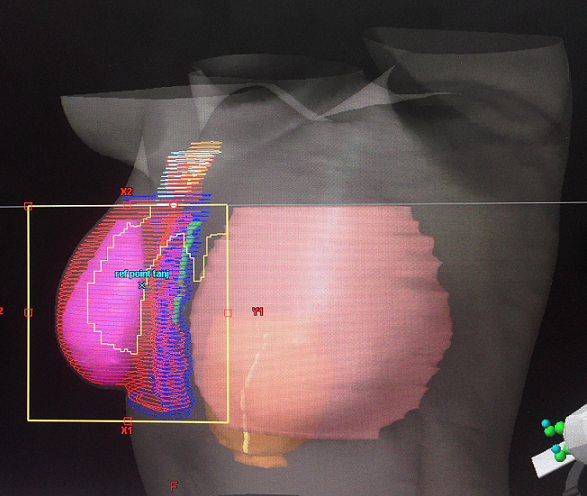

“ Meme kanserinde radyoterapi (RT), memenin alındığı (mastektomi) veya memenin korunduğu ameliyatlar sonrasında uygulanabilir. Memenin korunduğu cerrahi (MKC) girişimler sonrasında her durumda tüm meme dokusu ışınlanmaktadır. Kanserli hücreler koltukaltı lenf düğümlerine yayılmışsa meme dokusu ile beraber bu lenfatik bölgelerin de ışınlanması gerekmektedir. Mastektomi ameliyatlarından sonra ise bazı özel risk faktörlerinin varlığında göğüs duvarı ve/ veya çevre lenfatik alanlara radyasyon tedavisi uygulanmaktadır. Radyoterapi; iyonlaştırıcı radyasyon kullanarak (yüksek enerjili X ışınları) genellikle malign (iyi huylu olmayan) tümör hücrelerinin öldürülmesi işlemidir. Radyasyonun dozu, uygulama süresi ve uygulama alanı kontrollüdür. Radyasyon tedavisine cerrahi sonrası yara iyileşmesini takiben başlanabilir, bu genelde 4 haftalık bir süreyi ifade etmektedir. Hastaya eğer kemoterapi uygulanması gerekiyorsa önce 4, 6 veya 8 kür olarak kemoterapi uygulanır ve sonrasında radyoterapi uygulamasına başlanır. Kemoterapi uygulanmayacak ise, cerrahi girişim sonrası yara iyileşmesini takiben radyasyon tedavisine başlanabilir. Meme kanserinin tedavisinde sıklıkla uygulanan hormonoterapi ise genelikle radyasyon tedavisi ile birlikte uygulanabilmektedir.MKC uygulanmış olan ve koltukaltı lenf bezlerinde tümöre bağlı yayılım olmayan hastalarda sadece meme dokusuna, koltuk altında tümör metastazı olan hastalarda ise meme dokusu ile birlikte çevresel lenfatik bölgelere ( koltuk altı) RT uygulanmaktadır. Mastektomi uygulanan hastalarda ise, koltukaltı lenf düğümlerinde tümör metastazı olan, tümör boyutu 5 cm’den büyük, cerrahi sınır pozitifliği olan olgularda sadece göğüs duvarı ve/ veya lenf düğümleri ışınlanmalıdır. Radyasyon tedavisi planlama işlemi ile başlar, hastanın yatış pozisyonu belirlenir. Hasta bu pozisyonda tomografi cihazına yatırılır ve planlama tomografisi çekilir. Elde edilen tomografi kesitleri, üzerinde her kesitte tedavi edilecek olan bölgeler (meme / göğüs duvarı, lenf düğümleri) ve fazla radyasyondan korunması gereken organlar (kalp, akciğer) belirlenir. Tedavi bölgelerine maksimum doz verilirken kalp ve akciğer gibi normal dokular en az doza maruz kalacak şekilde radyasyondan korunmaya çalışılır. Özellikle sol meme tedavisinde kalp ve kalbi besleyen sol inen koroner arter dozları çok önemlidir. Bu dozları azaltmak için solunum ayarlı radyoterapi tekniği kullanılmalıdır. Tüm planlama süreci radyasyon onkolojisi uzmanı tarafından yönetilir. Radyasyon tedavisi toplamda 5-6 hafta sürmekte, ışınlama hafta içi beş gün ardışık olarak yapılarak, hafta sonu tedaviye ara verilmektedir. Radyasyon tedavisinden sadece siz ve sizin de doktorunuz tarafından belirlenen bölgeleriniz etkilenir. Tedavi sırasında radyasyon yaymazsınız, aileniz, çocuklarınız ile bir arada bulunabilir, birlikte zaman geçirebilirsiniz.Radyasyona bağlı olarak gelişen yan etkiler erken ve geç yan etkiler olarak iki gruba ayrılır. Erken yan etkiler; tedavi sırasında genelde 2. haftadan sonra ortaya çıkan ve tedavi bitiminden sonraki 2 hafta içinde azalarak iyileşen yan etkilerdir. Bunlar genelde cilt yan etkileridir. Tedavinin 2. haftasından itibaren deride kızarıklık, hafif ödem görülebilir. Tedavinin sonuna doğru derideki kızarıklık belirginleşir, soyulma, sulanma ve cilt renginde koyulaşma ortaya çıkabilir. Bu dönemlerde nemlendirici krem veya pomatlar ile cilt nemlendirilir. En iyi nemlendirici sudur, hastalara tedavi boyunca bol su içmeleri önerilmelidir. Erken yan etkiler geçicidir, hastalar bu konuda bilgilendirilmeli ve destek tedaviler ile rahatlatılmalıdır. Geç yan etkiler ise, tedavi bittikten 6-9 ay sonra ortaya çıkan, genelde yumuşak dokuda sertleşme ve damar duvarında kalınlaşmaya bağlı olarak ortaya çıkan yan etkilerdir. Meme dokusunda ödem, sertleşme, kolda hareket kısıtlılığı, kola giden sinirlerde hasarlanma ve ödem akciğerde sertleşme, kalbi besleyen sol koroner damarda tıkanmaya bağlı miyokart enfarktüsü ortaya çıkabilir. Meme cildinde ortaya çıkan ödem ve sertleşmeyi engellemek için memeye düzenli masaj uygulanmalıdır. Kol ödemini önlemenin en iyi yolu gereksiz koltukaltı operasyonundan ve geniş alan lenfatik ışınlamalardan kaçınmaktır. Kol ödemi hastanın hayatını olumsuz etkiler, geri dönüşümsüzdür. Kolda hareket kısıtlılığı ve kol ödeminden kaçınmak için hastalara düzenli olarak yapacakları hafif kol egsersizleri önerilebilir. Koltukaltı ameliyatı ve RT uygulanan kolda hiçbir cerrahi girişim yapılmamalı, kan alma, ilaç uygulama amaçlı damar yolu açılmamalı, manikür yapılmamalıdır. Kol ödemi gelişen hastalarda fizik tedavi ve rehabilitasyon uygulamalarından yararlanılmalı ve gerekirse bası giysileri önerilmelidir.Radyasyon tedavisi sırasında pamuklu ve bol giysiler tercih edilmeli, sıkı çamaşırlardan kaçınılmalıdır. Beslenme çok önemlidir. Hastalar karbonhitratların kısıtlandığı, protein ağırlıklı bir diyet ile beslenmeleri ve bol su içmeleri konusunda bilgilendirilmelidir. Sıklıkla en az 20 dakikalık açık hava yürüyüşleri yapılmalı, pilates, yoga ve gevşeme egzersizleri önerilmelidir. “HABER MERKEZİ